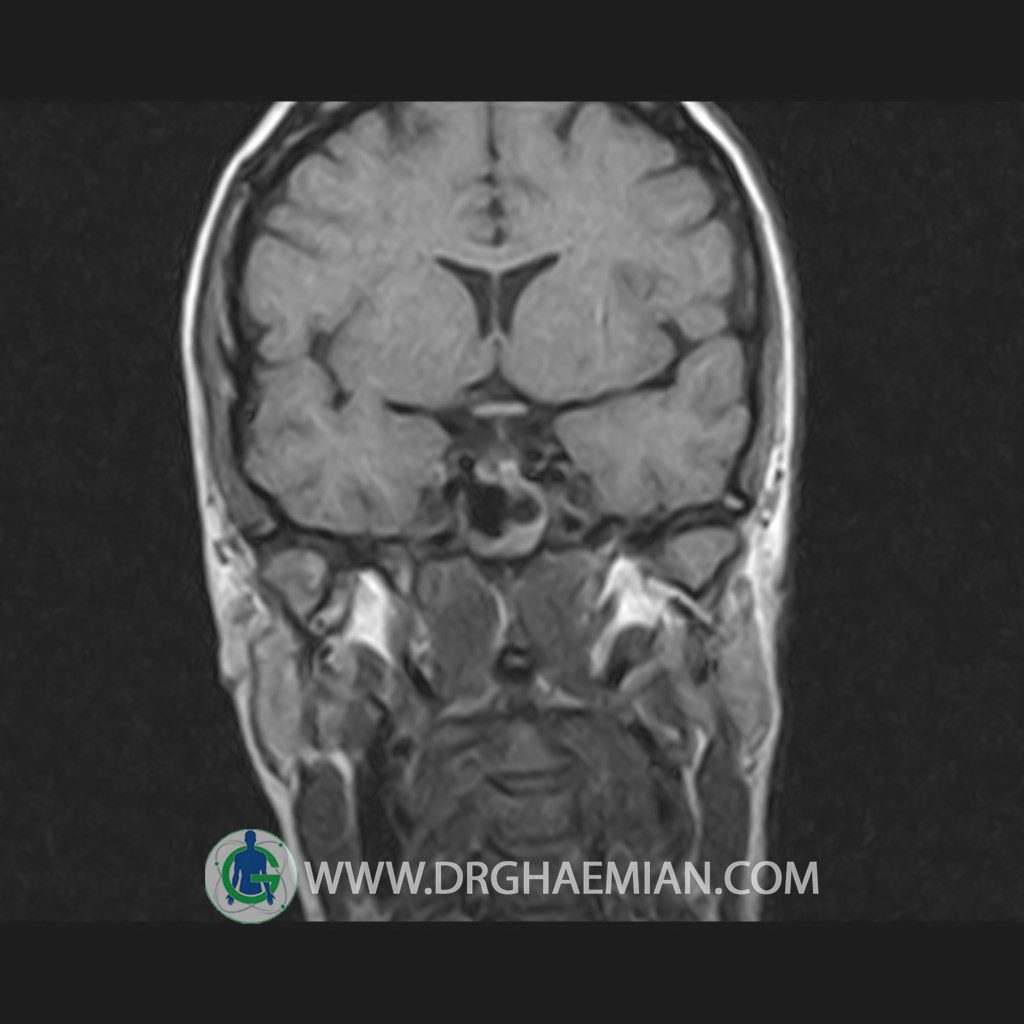

پزشکان اغلب از تصویربرداری ام آر آی برای تشخیص و درمان عارضه های پزشکی که فقط با استفاده از اشعه ایکس یا میدان مغناطیسی و امواج رادیویی قابل مشاهده است، استفاده می کنند. دستگاه ام آر آی تصاویر دقیق از ساختار های داخلی بدن ایجاد می کند. در این کیس هیپرپلازی هیپوفیز و آدنوم مشاهده می شود.

HYPOPHYSIS MRI

(with and without contrast)

Technique: Axial , coronal T1 , Axial , coronal , sagittal T2 , Axial, coronal T1 post Gd & 64 dynamic thin coronal slices.

The sella shows normal size , position and configuration .

The borders of its floor and walls are smooth and sharply defined .

The infundibulum is centered and of normal size .

The optic chiasm and suprasellar spaces appear normal .

The cavernous sinus and imaged portions of the internal carotid artery and carotid siphon are unremarkable .

Evaluable portions of the neurocranium show no abnormalities .

The sphenoid sinus is clear and pneumatized .

– Mild convexity at superior border of pituitary gland with post contrast homogeneous enhancement suggestive for pituitary hyperplasia & iso signal adenoma

is seen